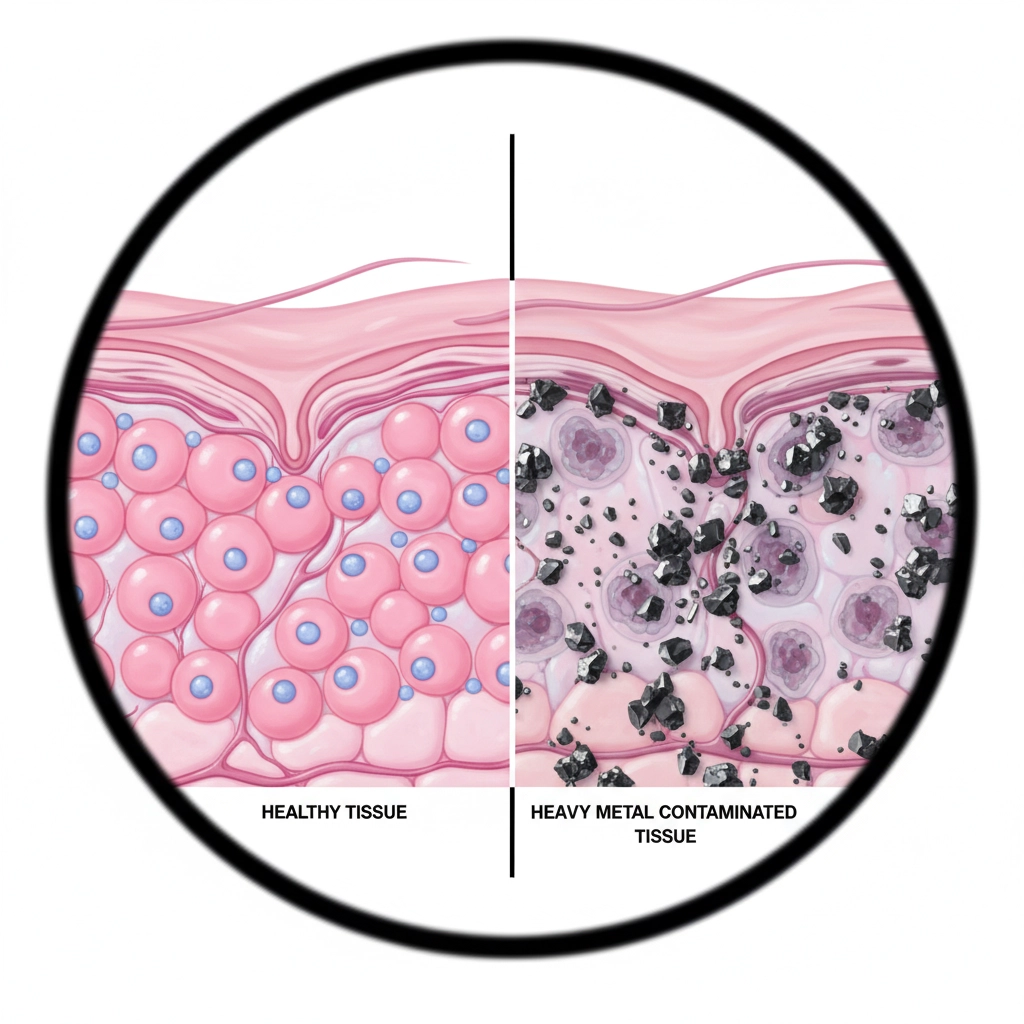

Heavy Metal Contamination: A Silent Threat

Many popular green clay powders contain dangerous levels of heavy metals. Aztec Secret Indian Healing Clay, despite its popularity, has been found to contain concerning amounts of lead, mercury, and arsenic. These toxic substances can accumulate in your body over time, potentially causing serious health issues.

The shocking truth? Most consumers have no idea they're applying heavy metals to their skin.

Heavy Metal Testing: The Clayer Guarantee

While brands like Aztec Secret and NOW Solutions offer no heavy metal testing guarantees, Clayer undergoes rigorous third-party testing for lead, mercury, cadmium, and arsenic. Every batch is certified safe.

This isn't just about marketing, it's about your health. Heavy metals can:

- Accumulate in organs over time

- Disrupt hormonal balance

- Affect cognitive function

- Compromise immune system response